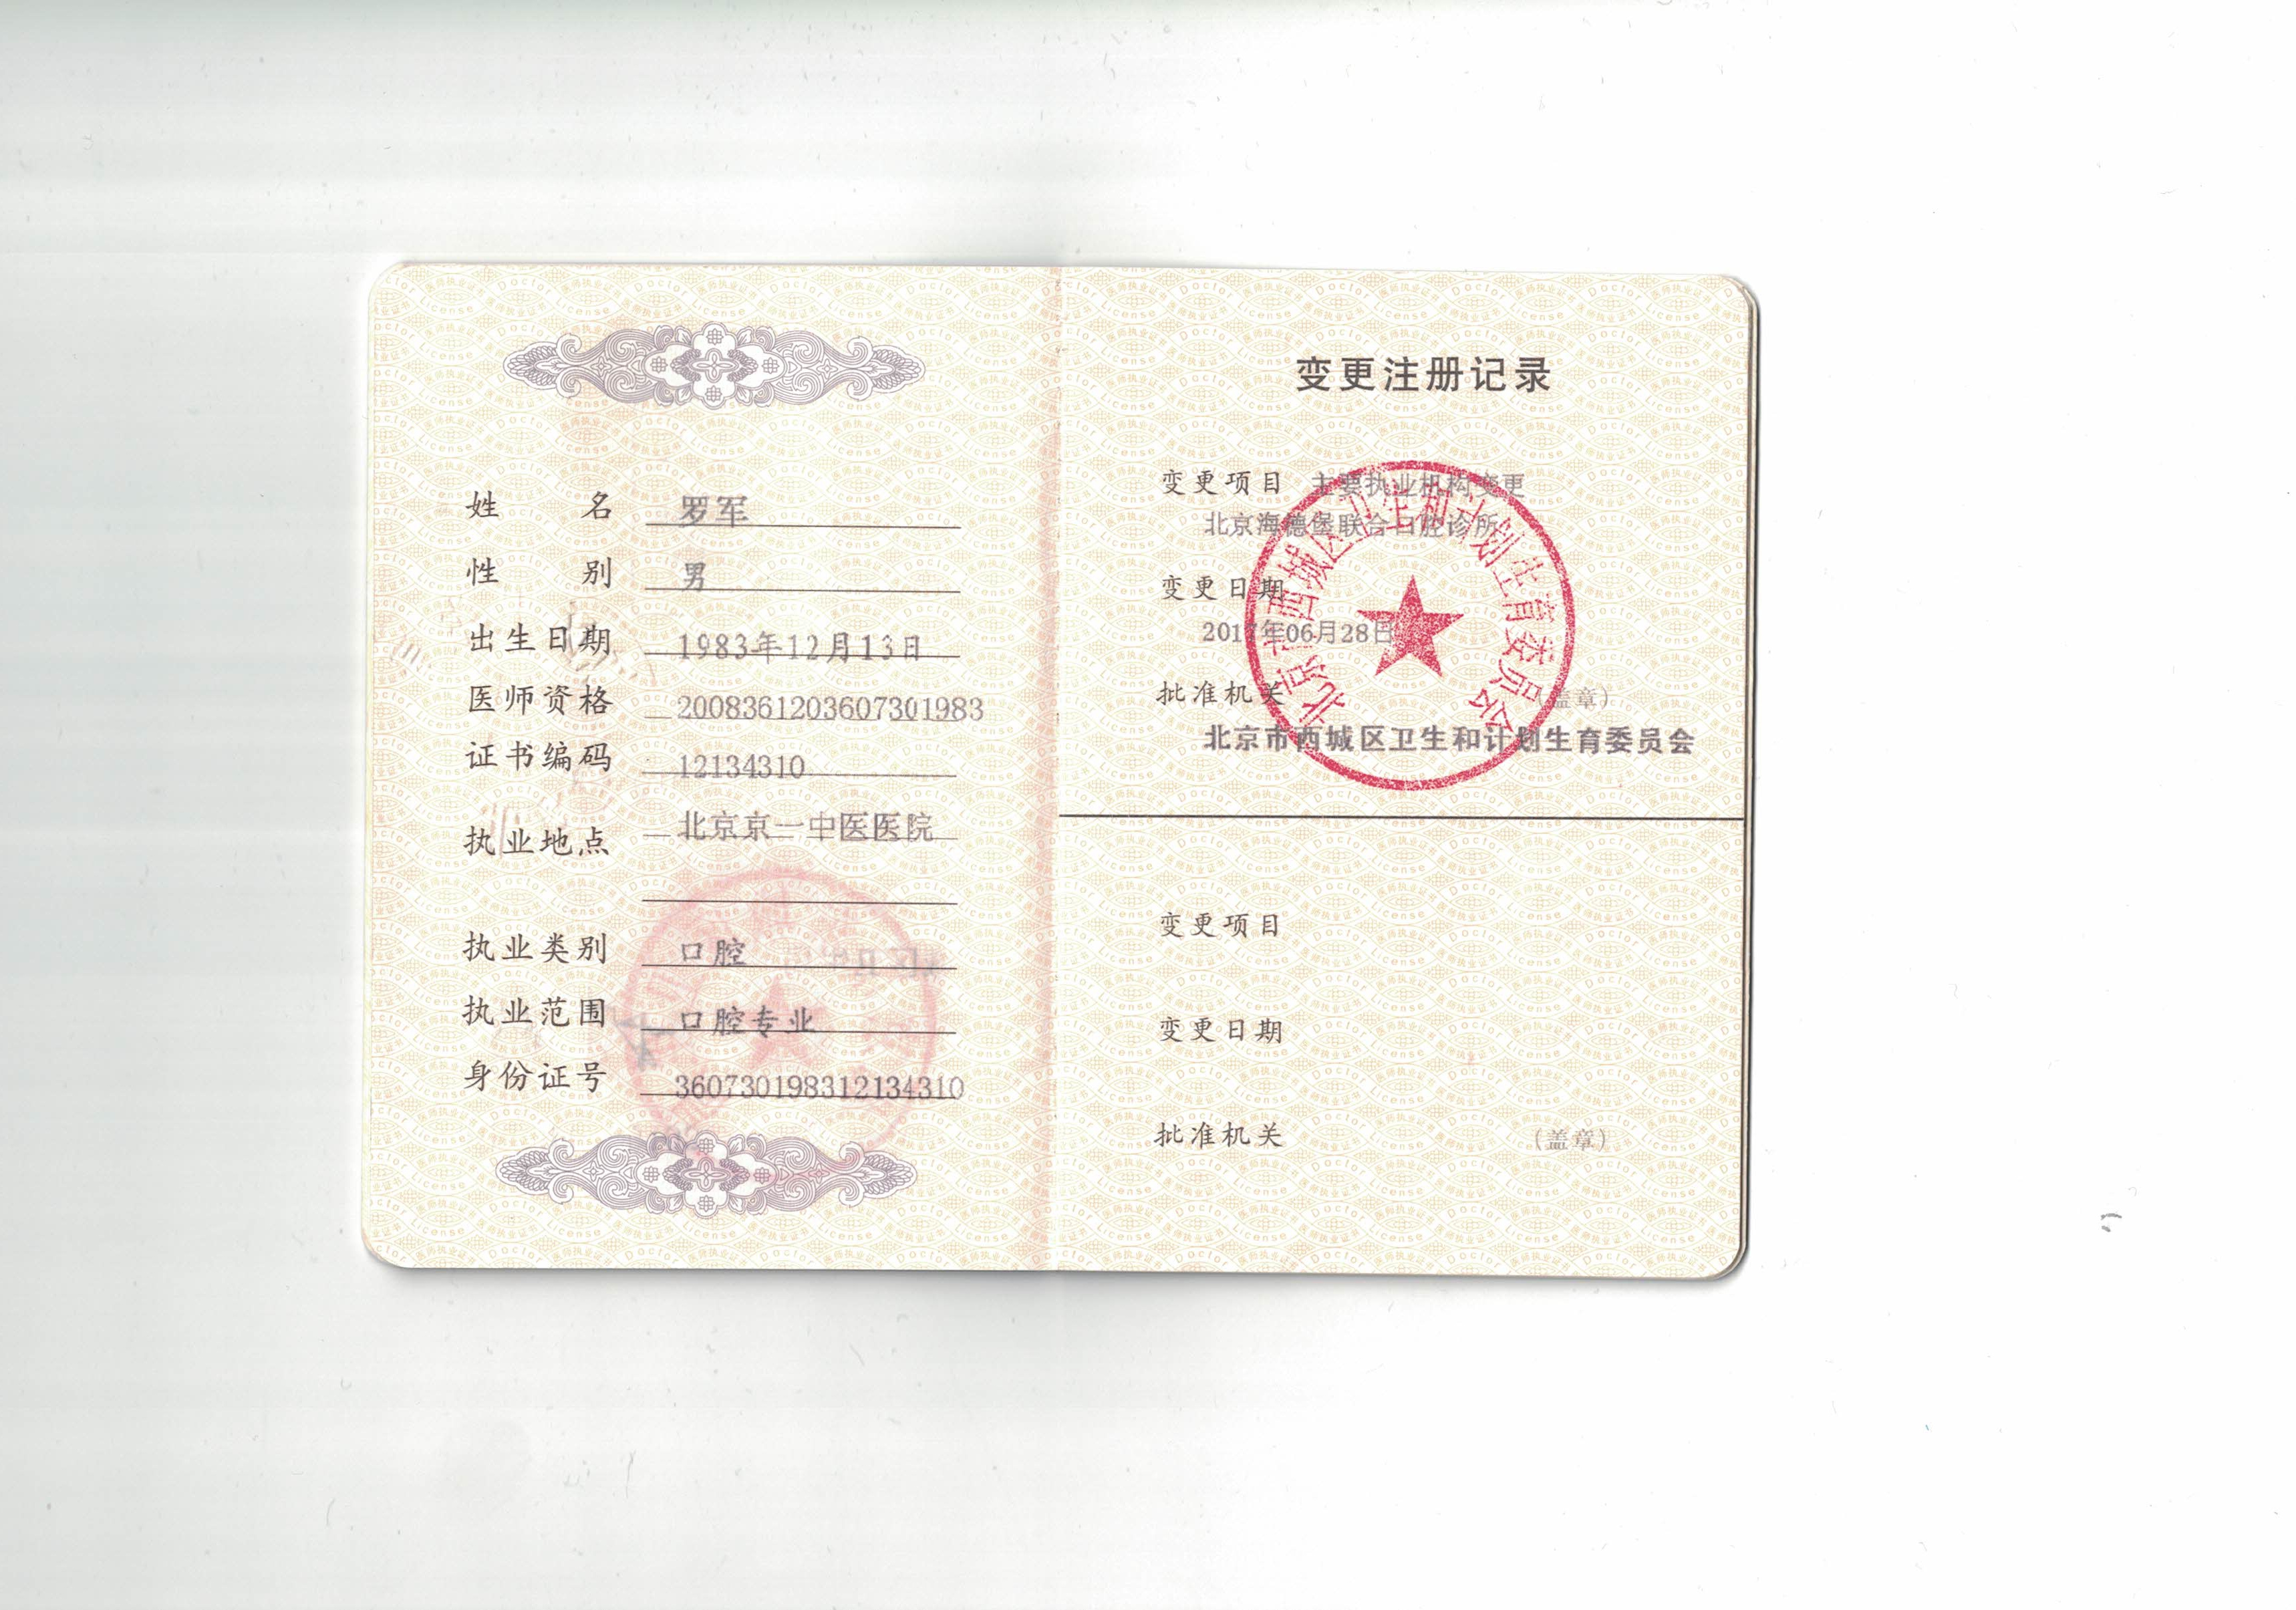

② 罗军:德国法兰克福大学硕士,精通数字化种植和即拔即种